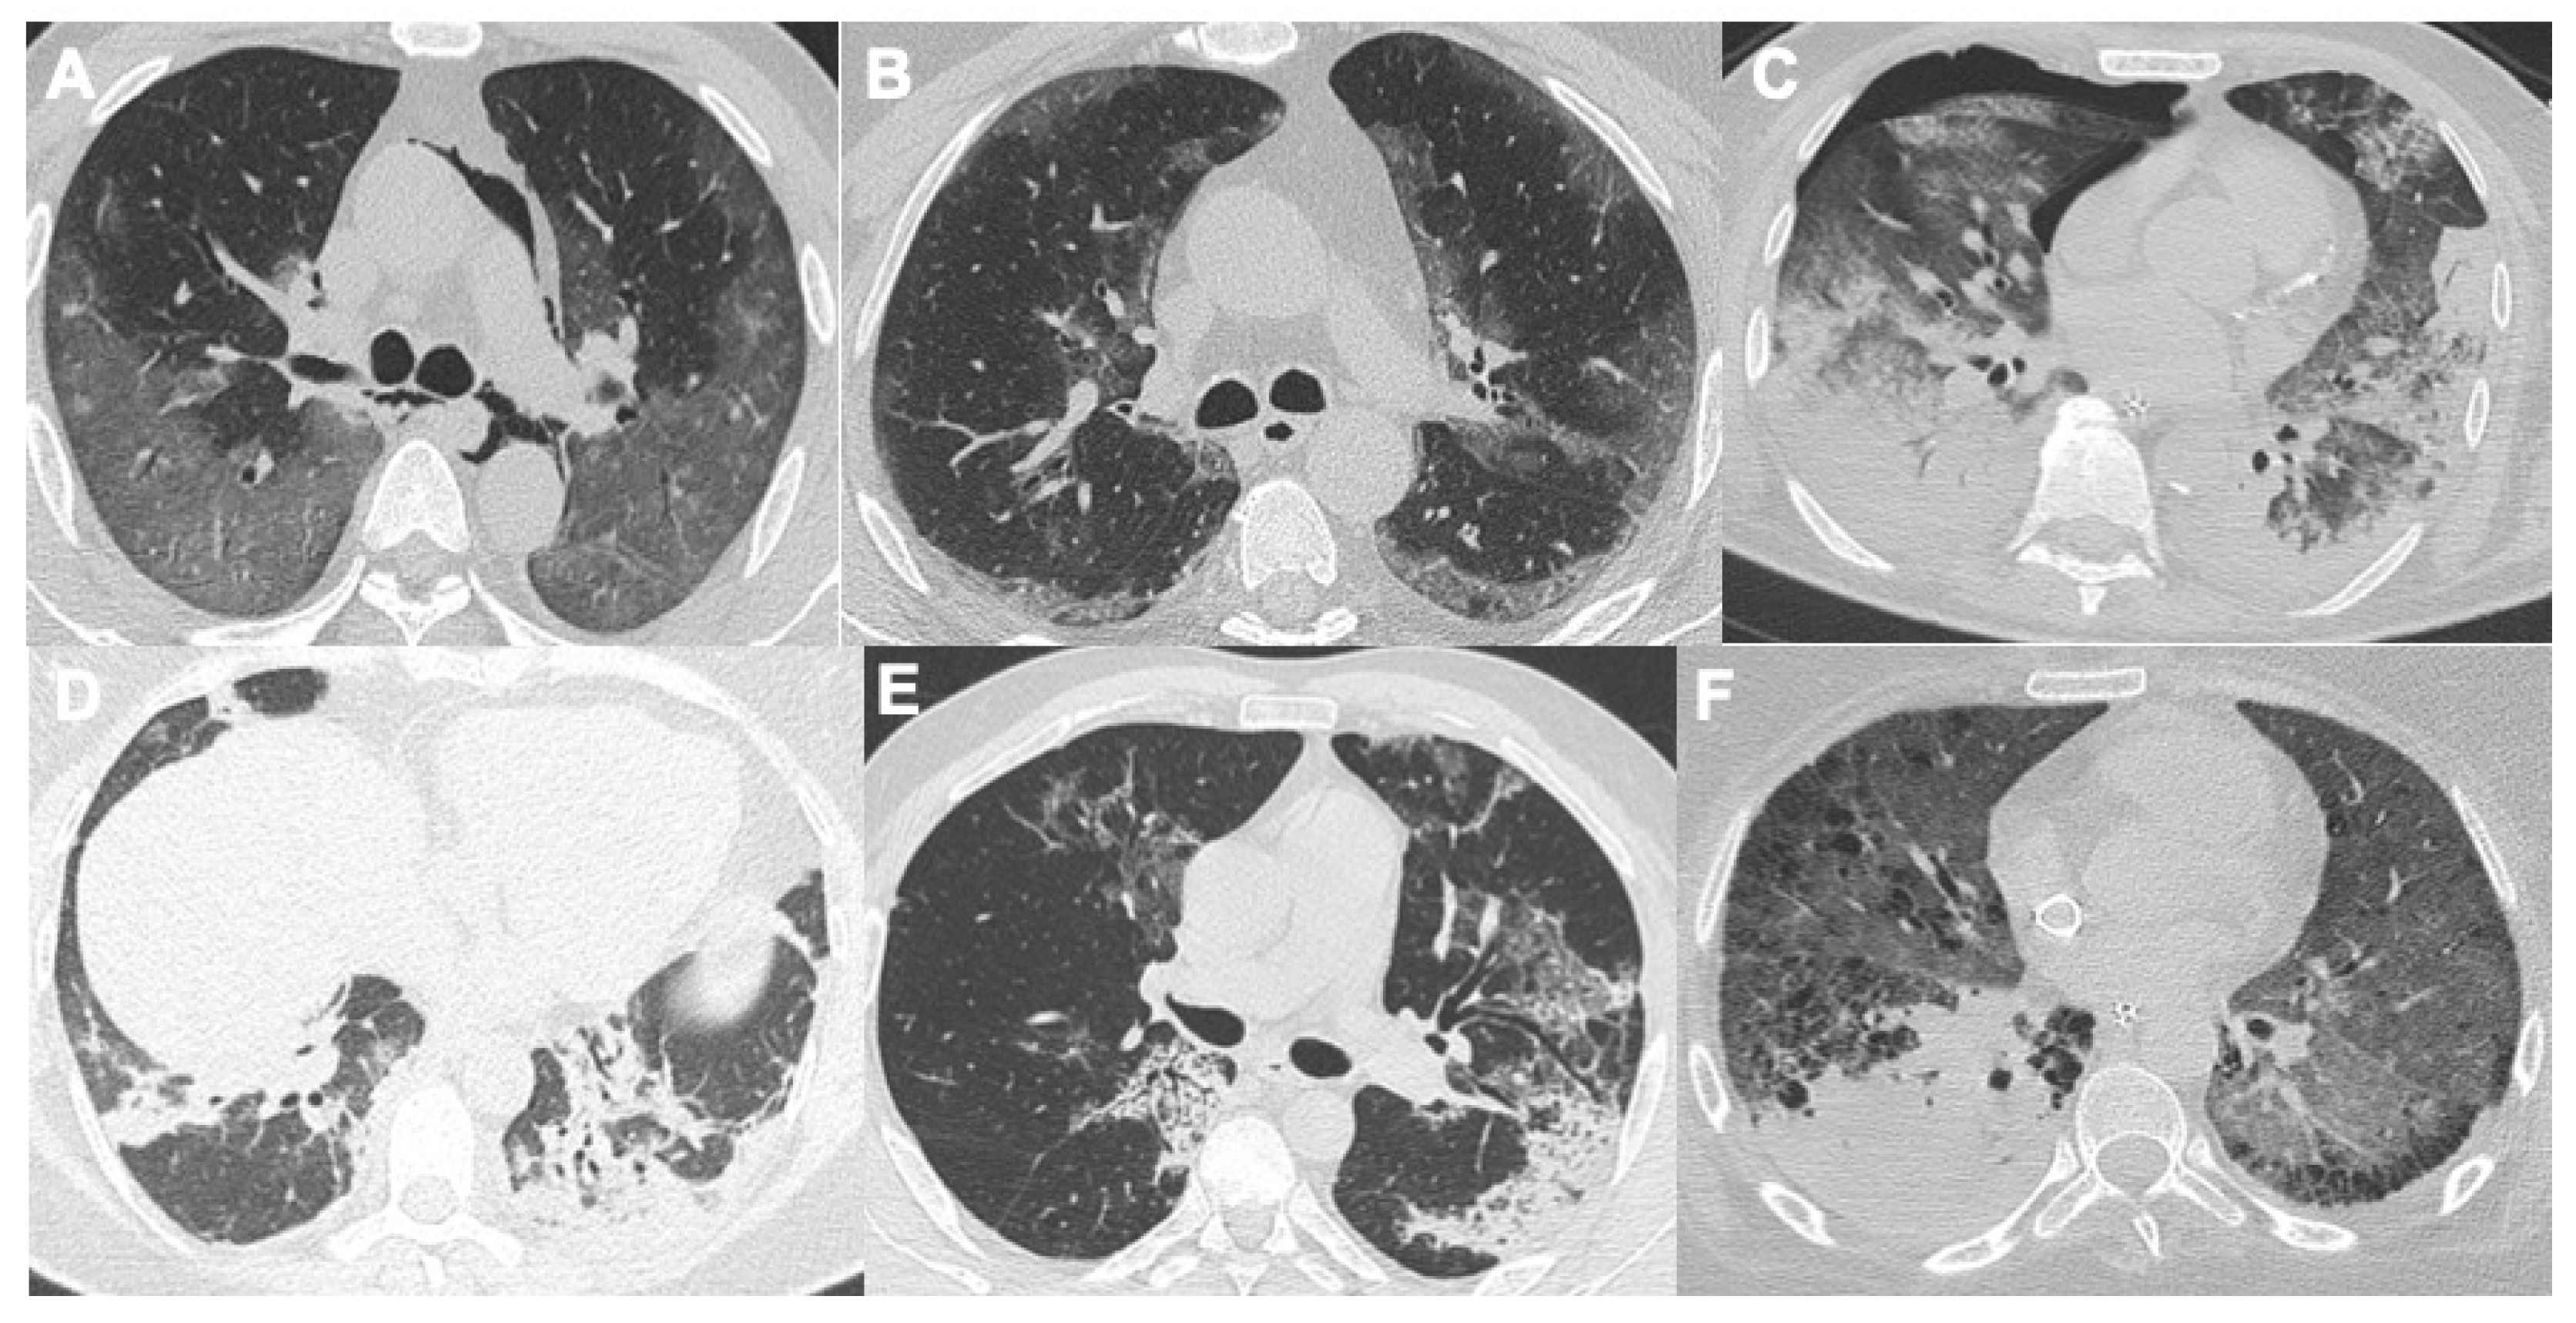

2. COVID-19 and Lung Disease

2.1. Pneumonia

2.2. Acute Respiratory Disease Syndrome

2.3. Pulmonary Embolism